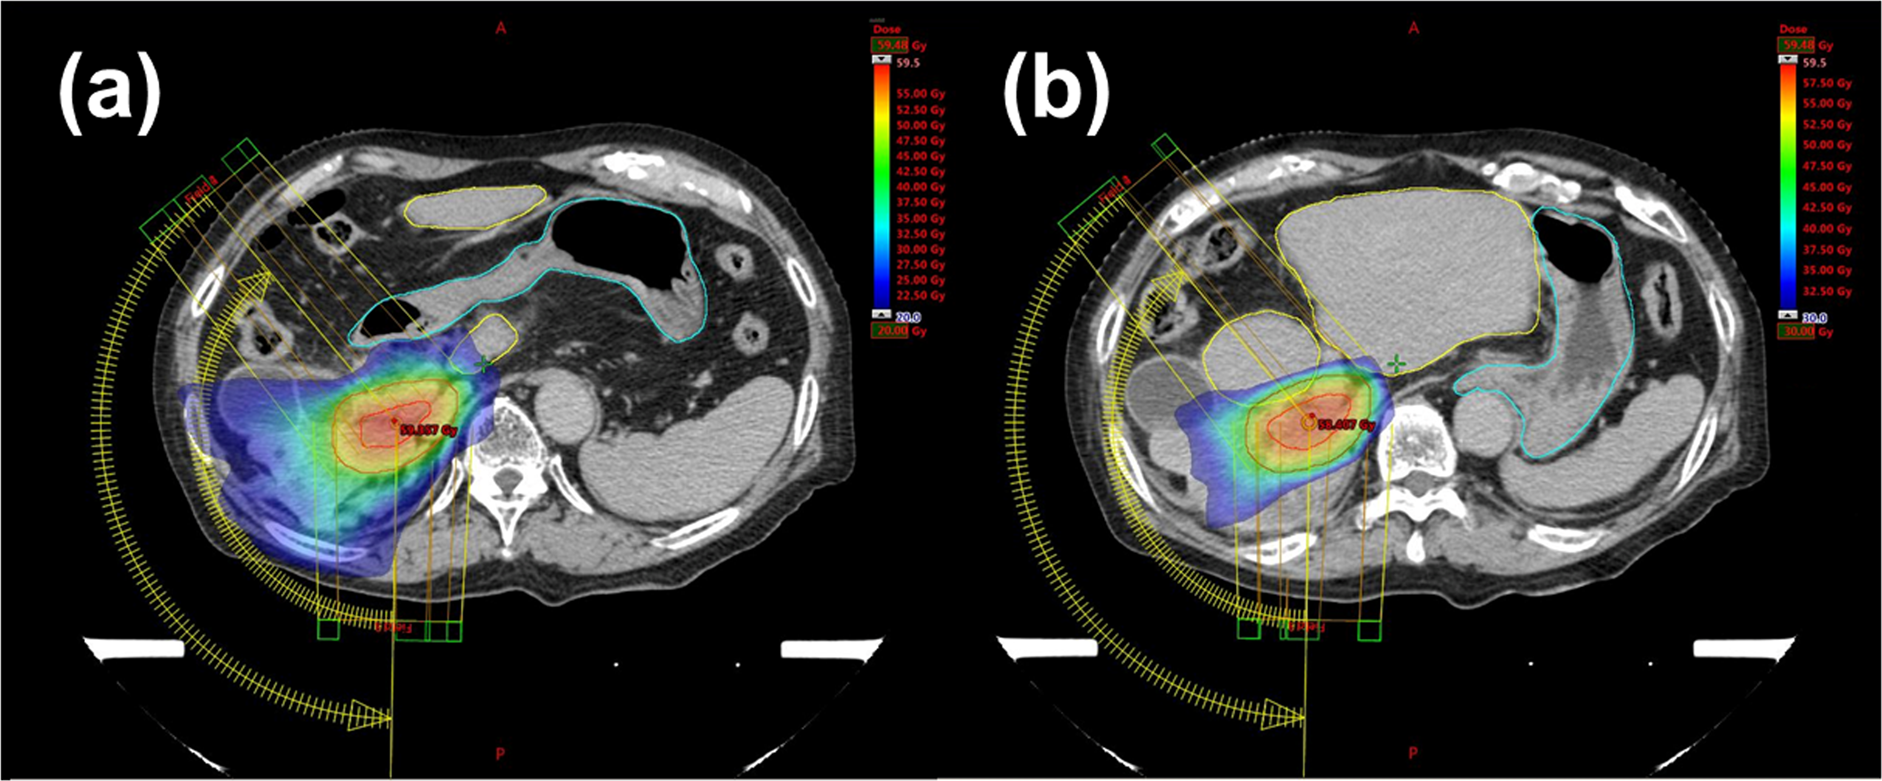

Figure 2

Example of a treatment plan (patient F) showing the colour wash dose distribution; (a) 20 Gy and above, and (b) 30 Gy and above. Radiation doses to the stomach and duodenum (marked by a light blue line) were less than 20 Gy; irradiation beyond the resection line (remnant liver: marked by a yellow line) was also reduced to less than 30 Gy.